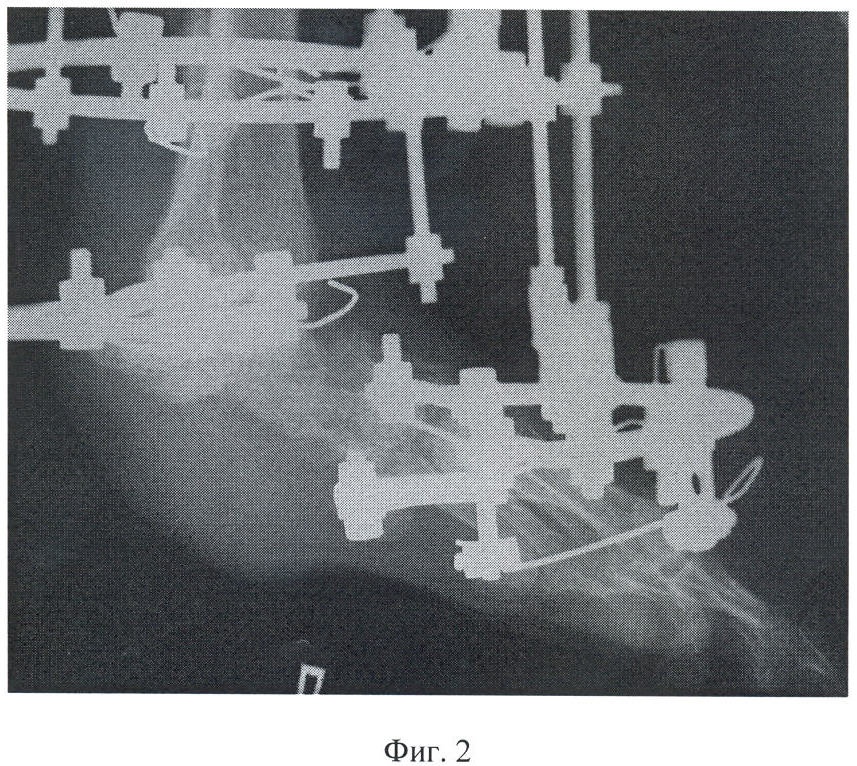

Фиг.2 – рентгенограмма левой стопы больного К. после выполнения остеосинтеза и секвестрнекрэктомии с удалением пяточной кости;

Для ликвидации остеомиелитического процесса больному первоначально выполнена радикальная секвестрнекрэктомия с удалением пяточной кости, удаление хрящей в голеностопном и таранно-ладьевидном суставах; остеосинтез аппаратом внешней фиксации.

В ходе операции после анестезии и обработки операционного поля три спицы провели на уровне проксимальной, две – средней и три – дистальной трети берцовых костей. Таранную кость фиксировали двумя спицами, кости предплюсны и плюсневые кости – тремя спицами. В натянутом состоянии спицы закрепили на установленных в их проекции опорах, которые соединили между собой резьбовыми стержнями и шарнирными узлами.

Через разрез мягких тканей по наружной поверхности стопы осуществили доступ к пораженному отделу стопы и произвели радикальную секвестрнекрэктомию с удалением пяточной кости. Одновременно сняли хрящ с суставных поверхностей голеностопного и таранно-ладьевидного сочленений. После выполнения контрольной рентгенографии рану ушили с установкой дренажной системы.

В послеоперационном периоде в течение 48 дней осуществляли взаимокомпрессию костей голеностопного и таранно-ладьевидного сочленений до получения артродеза этих суставов.

После этого в ходе повторного оперативного вмешательства выполнили остеотомию большеберцовой кости на уровне проксимальной и дистальной трети, а также остеотомию шейки таранной кости. При этом остеотомию дистального отдела большеберцовой кости произвели с выделением концевого фрагмента, который вместе с синостозированным с ним фрагментом таранной кости по своим размерам соответствовал размерам заднего отдела стопы.